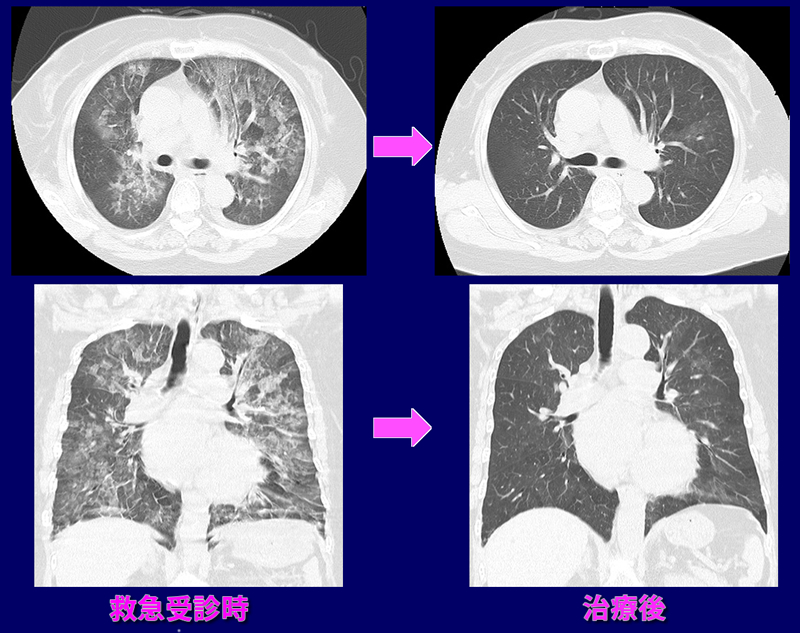

夜間10時頃、息苦しさ出現。看護師付き添いで緊急受診。血液酸素飽和度70%前後、頻呼吸、呼吸困難強く、酸素投与下にCT検査。著明な肺水腫認め(左側画像)、急性心不全として,酸素投与と利尿剤投与。約2時間30分後症状改善し、帰宅。翌日確認のためCT検査実施(右側画像)。肺水腫は消失。以後外来で9年間心不全の治療と観察をしているが心不全は生じていない。

急性心不全肺水腫